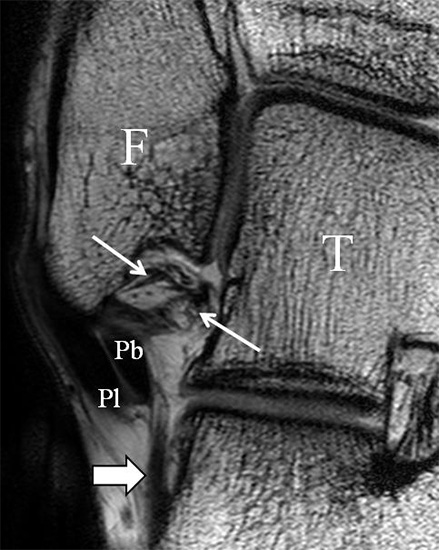

b. T2 fs axial. Infraktion des hinteren Volkmann‘schen Dreiecks (schmale, weiße Pfeile). Hier inserierende, intakte, hintere Syndesmose (breite, weiße Pfeile).

Abbildung 18b

Das Ligamentum tibiofibulare posterius (hintere Syndesmose) verläuft flacher und geht nach kranial in das Ligamentum tibiofibulare interosseus und nach kaudal in das Ligamentum intermalleolare posterius über. Letzteres bildet ein artikuläres Labrum zwischen Trochlea und Talus 9.

Da also die hintere Syndesmose an der posterioren Tibia inseriert, entspricht eine Fraktur oder Infraktion des hinteren Volkmann`schen Dreiecks funktionell einem knöchernen Ausriss des Ligamentum tibiofibulare posterius (Abb. 18 a und b). Aufgrund der Koinzidenz von Syndesmosenläsionen mit Innenbandverletzungen ist bei der Beurteilung gesondert auf solche zu achten.